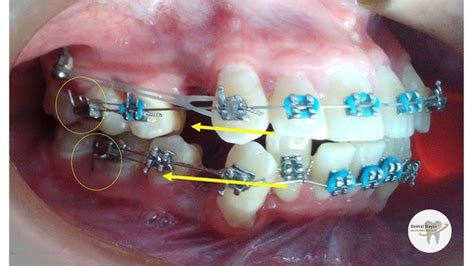

El protocolo de colocación es relativamente sencillo pero requiere precisión: el especialista selecciona la longitud adecuada de cadena (viene en rollos y se corta la cantidad de eslabones necesarios) para abarcar el tramo deseado, ya sea entre dos dientes específicos o a lo largo de un segmento completo de la arcada. Luego, con ayuda de un instrumental (como pinzas ortodónticas), fija un extremo de la cadeneta en el gancho o aleta de un bracket en un diente terminal del segmento a mover, y va estirando la cadena enganchándola sucesivamente en cada bracket intermedio hasta llegar al diente del otro extremo. Cada eslabón suele encajar sobre las aletas del bracket (las mismas donde se colocan ligaduras) o en ganchos auxiliares si el bracket los tiene. Al enganchar la cadena eslabón por eslabón, esta queda tensionada; el ortodoncista suele observar cuánta tensión se está aplicando para no excederse. Se puede ajustar enganchando la cadena en todos los dientes intermedios o, en ocasiones, omitiendo algún diente para reducir la fuerza si es necesario (por ejemplo, enganchar en primero y último de un tramo para un tirón más suave que si se engancha en cada bracket intermedio).